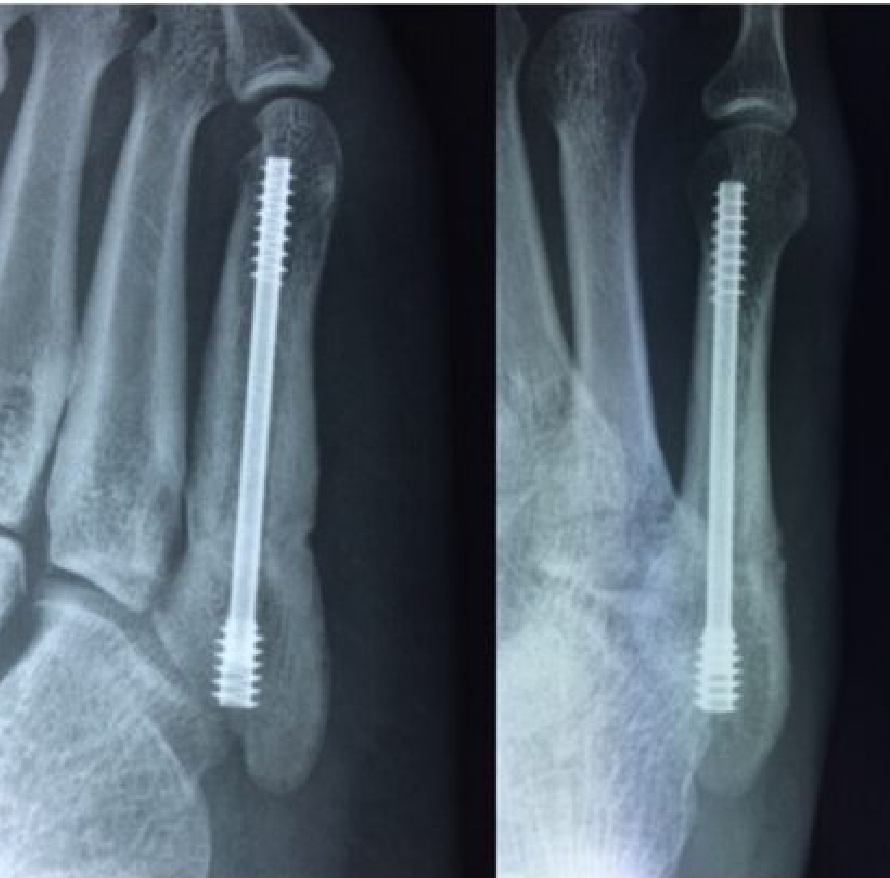

2020-12-09 スポーツ整形 ページ内リンク 第5中足骨骨折(ジョーンズ骨折)【スポーツ整形外科】 第5中足骨骨折(ジョーンズ骨折)【スポーツ整形外科】 サッカーやバスケット等の切り返しの多い競技にしばしば発生する。⇒スクリューによる固定で2〜3か月で復帰。 術前 術後 術後12週間 関連ページ スポーツ整形 一覧へ戻る